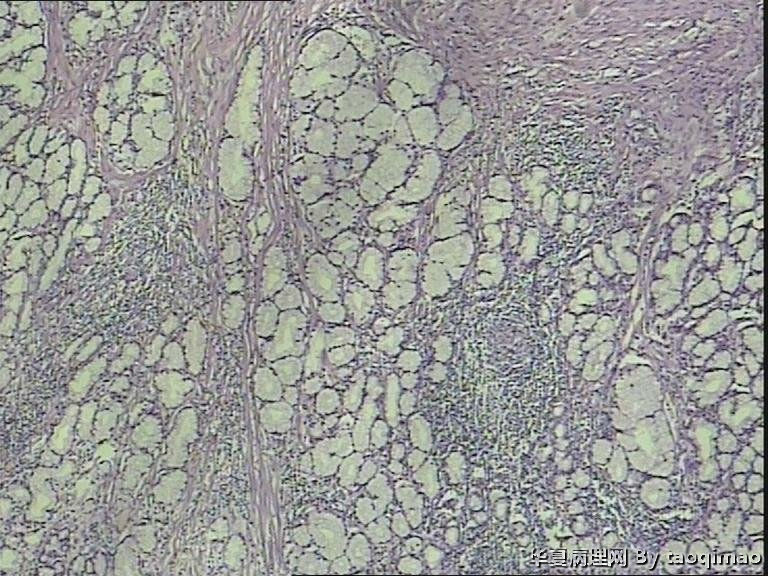

• 胃溃疡?图1

补取的组织

79岁女,胃溃疡,切除胃大部分,与脾有粘连,胃小弯侧可见一溃疡3x2.5x2cm,并且局部胃粘膜增厚,呈皮革胃样外观,切面灰白似粘液样。

巨大溃疡临床诊断,可是看了间质很浆糊,希望老师们给指点些

胃溃疡,黏液变,没看到明确的上皮样细胞